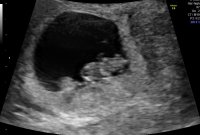

Krysser fingrene for at det vokser akkurat som det skal7+0 utifra mens, fosteret var rundt 7mm, så mellom 6+5 og 7+0 ble jeg målt til. Satser på at baby har blitt litt større i morgen![]()

Bamsemums på 15mm i dag7+0 utifra mens, fosteret var rundt 7mm, så mellom 6+5 og 7+0 ble jeg målt til. Satser på at baby har blitt litt større i morgen![]()

Hurra! Hvor mange uker ble du estimert til? Stemte det overens med det du tidligere har beregnet?Bamsemums på 15mm i dag![]()

Utifra målingene med 15mm så ble jeg målt til 8+0, er 7+6 i dagHurra! Hvor mange uker ble du estimert til? Stemte det overens med det du tidligere har beregnet?